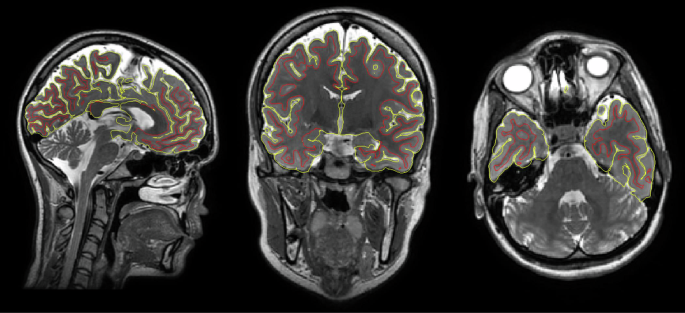

MRI data was processed in the recon-all stream of FreeSurfer version 6.0.0 (https://surfer.nmr.mgh.harvard.edu)79. Briefly, this processing stream includes removal of non-brain tissue, Talairach transformation and intensity non-uniformity correction. Intensity information was used to reconstruct the inner (i.e., the gray/white matter boundary) and outer (i.e., the gray matter/cerebrospinal fluid boundary) surfaces of the cerebral cortex. Quality control and editing were conducted by trained research assistants following standard FreeSurfer procedures. At this stage, no participants were excluded. The T1w/T2w-ratio was computed using an approach previously found to have high test-retest reliability41. Briefly, this approach performs post hoc corrections for field inhomogeneities, partial voluming, and the presence of surface outliers, and intensity normalization using WhiteStripe80, which uses intensity values in normal-appearing white matter to harmonize T1w/T2w-ratio values. The mean T1w/T2w-ratios were extracted in three bilateral regions of interest in the Destrieux atlas81: The anterior transverse temporal Heschl’s gyrus, the transverse temporal sulcus, and the temporal plane of the superior temporal gyrus. Cortical labels were visually inspected to ensure correct placement. No subjects were excluded due to poor cortical labeling. For the main analysis, we defined two main regions of interest; the Heschl’s gyrus, referred to as the primary auditory cortex (AC1) in the manuscript, and the combined transverse temporal sulcus and superior temporal gyrus, referred to as secondary auditory cortex (AC2) in the manuscript. The T1w/T2w-ratio was calculated as an area-weighted mean across hemispheres and sub-regions. See Supplementary Note 1 for a discussion around parcellation of the AC and Supplementary Note 2 for details on how T1w/T2w-ratio was calculated. Supplementary Figs. 1 and 2 show the AC1 (Heschl’s gyrus) and AC2 (transverse temporal sulcus - superior temporal gyrus) regions of interest. Figure 1 shows example T1- and T2-weighted volumes and the T1w/T2w-ratio volumes.

In the left column, T1-weighted volumes are shown (upper: coronal view, lower: sagittal view). In the middle column, T2-weighted volumes are shown. In the right column, T1w/T2w-ratio volumes are shown. The cortical surfaces based on FreeSurfer reconstruction are shown in red lines representing the outer cortical surface (i.e., the pial surface) and yellow lines represent the inner cortical surface (i.e., white matter surface).